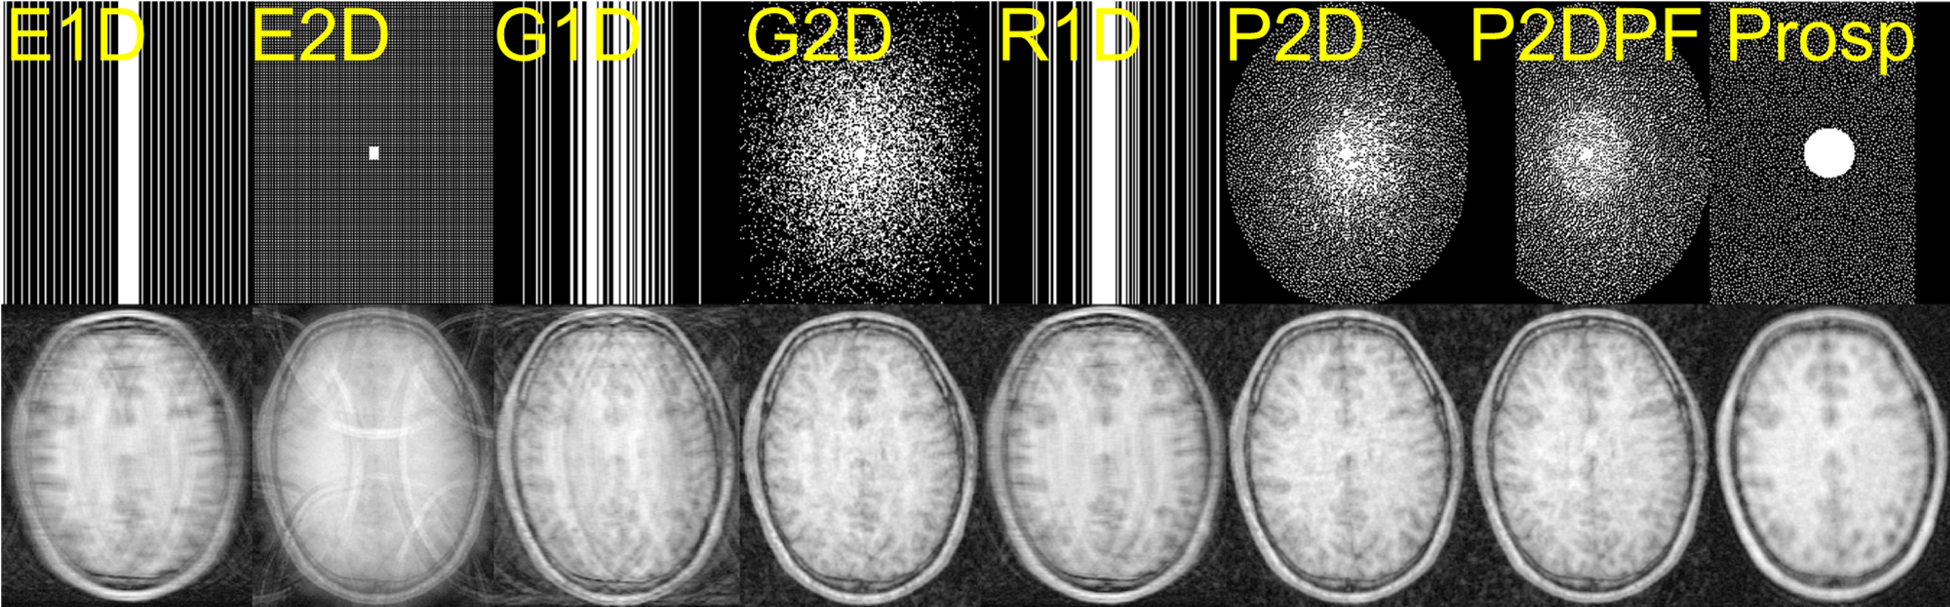

The partial_fourier parameter sets a percentage of outer k-space that is not sampled, resulting in a partially sampled k-space. An illustrative overview of the undersampling options is provided in Fig. 3.

Refer to caption

Figure 3: Overview of undersampling options in ATOMMIC. From left to right, columns one to seven present retrospective undersampling using Equispaced 1D (E1D), Equispaced 2D (E2D), Gaussian 1D (G1D), Gaussian 2D (G2D), Random 1D (R1D), Poisson 2D (P2D), and Poisson 2D with 20% Partial Fourier (P2DPF) masking, respectively. Note that Partial Fourier can be applied to any masking. The last column presents prospective undersampling (Prosp) using the Calgary-Campinas 359 dataset default 2D Poisson mask (Beauferris et al. (2022)).